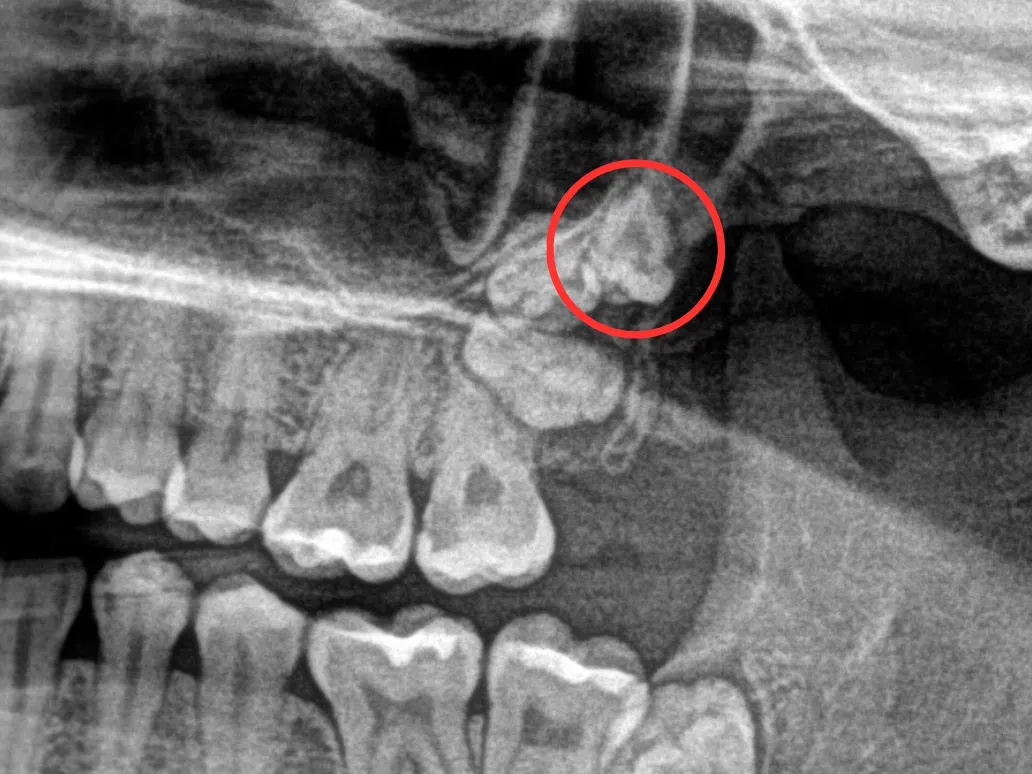

Każda ekstrakcja zęba rozpoczyna się od dokładnej diagnostyki. Najpierw przeprowadzam szczegółowy wywiad medyczny, aby poznać historię zdrowia pacjenta, przyjmowane leki i ewentualne alergie. Następnie wykonuję badanie jamy ustnej. Kluczowym elementem jest jednak zdjęcie rentgenowskie najczęściej pantomograficzne (przeglądowe całej szczęki i żuchwy) lub punktowe (konkretnego zęba). Dzięki RTG mogę ocenić kształt i liczbę korzeni, ich położenie względem sąsiednich struktur (np. zatoki szczękowej, nerwu) oraz stan kości otaczającej ząb. Na podstawie tych informacji tworzę precyzyjny plan działania.

Zęby zatrzymane i ósemki dlaczego często muszą być usunięte?

Zęby zatrzymane to takie, które mimo iż są w pełni wykształcone, nie wyrżnęły się prawidłowo i pozostają w kości. Najczęściej dotyczy to zębów mądrości, czyli ósemek. Ósemki często nie mają wystarczająco miejsca w łuku zębowym, wyrzynają się pod niewłaściwym kątem, uciskając sąsiednie zęby, powodując ból, stany zapalne, torbiele, a nawet uszkodzenia korzeni zębów sąsiednich. W takich przypadkach ich usunięcie, często chirurgiczne, jest niezbędne.

Wyróżniamy dwa główne typy ekstrakcji. Ekstrakcja prosta to ta, którą opisałem powyżej ząb jest widoczny w jamie ustnej i można go usunąć za pomocą kleszczy i dźwigni bez konieczności nacinania dziąsła czy usuwania kości. Natomiast ekstrakcja chirurgiczna, zwana dłutowaniem, jest zabiegiem bardziej skomplikowanym. Jest konieczna w przypadku zębów zatrzymanych (np. ósemek, które nie wyrżnęły się w pełni), zębów z nietypowymi, zakrzywionymi korzeniami, zębów złamanych pod linią dziąsła, czy gdy ząb jest silnie zrośnięty z kością. Dłutowanie wymaga nacięcia dziąsła, a czasem usunięcia fragmentu kości otaczającej ząb, aby umożliwić jego bezpieczne usunięcie. Jest to zabieg bardziej inwazyjny, ale również wykonywany w znieczuleniu miejscowym i w pełni bezpieczny w rękach doświadczonego chirurga stomatologicznego.